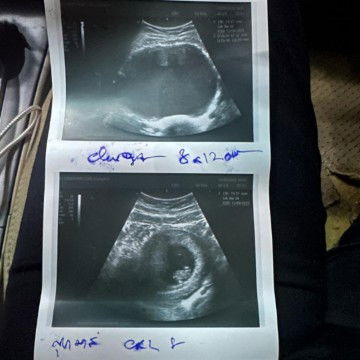

ท้องได้8สัปดาห์4วันตรวจเจอพร้อมกับซีส8-12เซนต์อันตรายต่อเด็กไหมค่ะ

ท้องได้8สัปดาห์4วันตรวจเจอพร้อมกับซีส8-12เซนต์อันตรายต่อเด็กไหมค่ะ#ลูกคนแรก #ขอบสำหรับคอมเม้นล่วงหน้าค่ะ